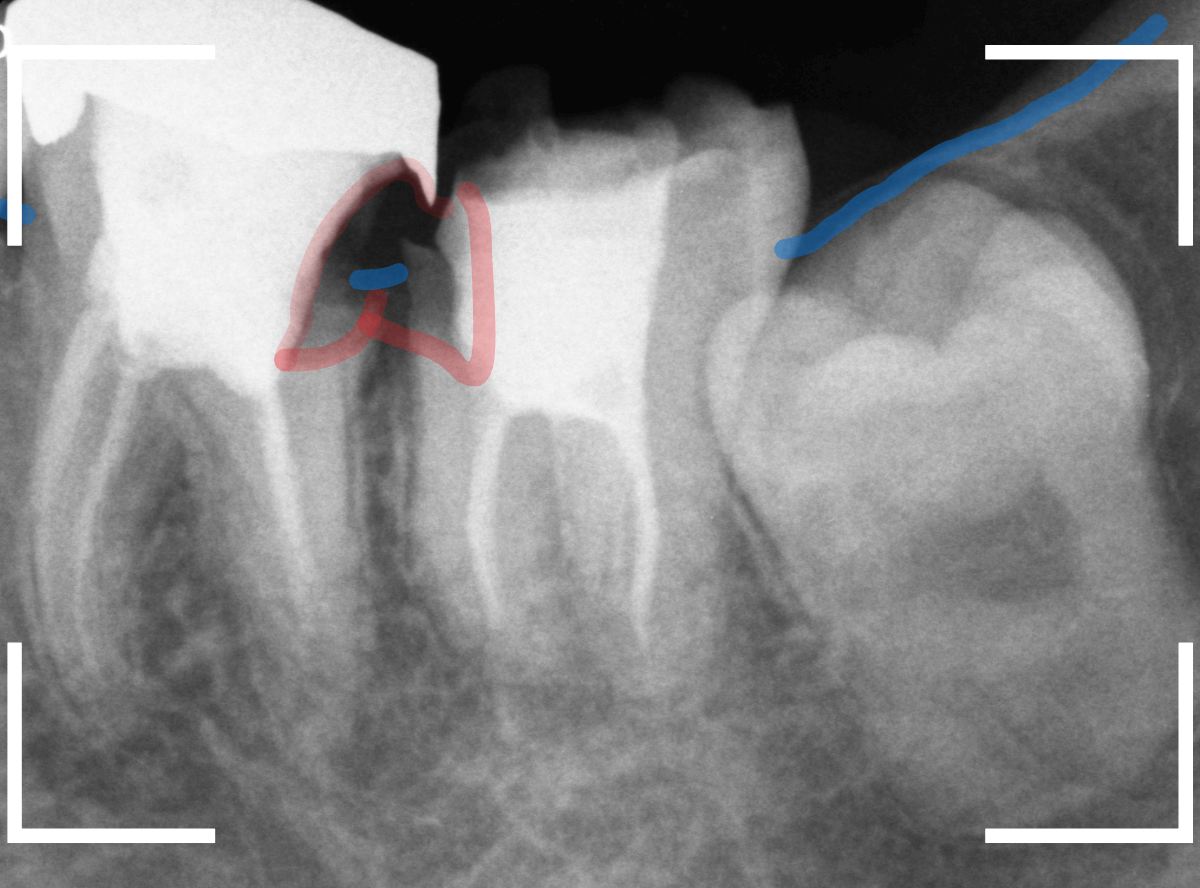

レントゲン写真です。

レジンの下が虫歯になっているのがわかります。

レントゲン写真で確認します。

青い線が歯の神経、赤い線が虫歯です。

おやしらずがあった際にはわかりづらかったですが、歯の後ろ側のおやしらずが重なっていたところが虫歯になっているのがわかります。

おやしらずが原因で、このように手前の歯が虫歯になってしまう事が多いために、抜歯を勧められる事が多いのです。

そして、虫歯の部分におやしらずが被さっていたために、しみる症状などを感じなかったのです。